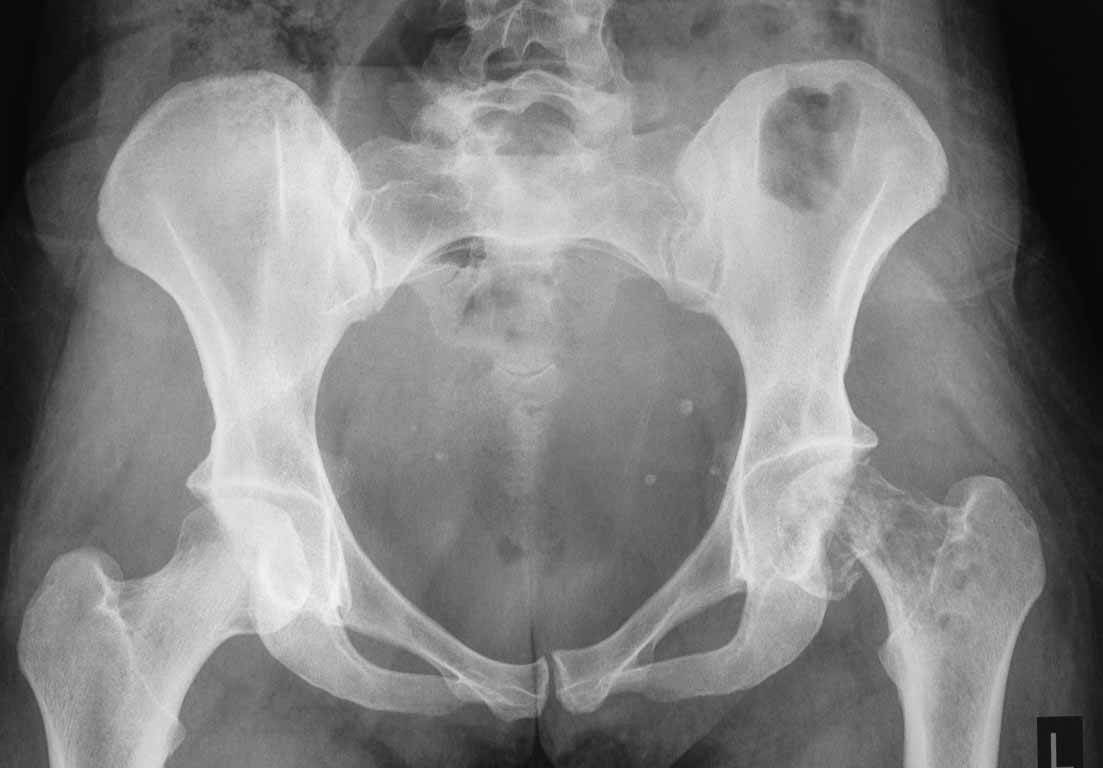

Здравствуйте, коллеги!Пациентка 35 лет, перелом на фоне метастаза в шейку бедра. Онкология молочной железы 2 года назад, оперирована, курсы химии и лучевой терапии. 2 месяца назад появились боли в области левого т\бедренного сустава, 10 дней назад диагностирован патологический перелом. Планировался курс химии в ближайшее время. По данным обследования процеес в правом бедре, и надвертлужной области справа. Других метастазов в настоящее время не выявлено. Имеет ли смысл эндопротезирование левого сустава? До или после химиотерапии?

День добрый! Александр! Вероятно догадываюсь о ком идет речь. Для определения объема вмешательства необходимо выполнить ряд обследований: КТ-даст объем костной деструкции проксимального отдела бедра,а возможно и впадины-определиться с объемом костной резекции и конструкцией эндопротеза; МРТ- даст наличие или отсутствие мягкотканного компонента, а также степень миграции метастаза по костномозговому каналу (часто видели "сусулю" на 10-12 см дистальнее очага),ангиографию-для определения характера васкуляризации опухоли, цитологию-для подбора химиотерапии, сцинтиграфию-для обнаружения других очагов.Возможно онкологи добавят еще что-то. Если метастаз единичный, необходимо облучение и рациональная химия (но наш онкоцентр категорически не берет на лечение не ходячих больных), после восстановления показателей гомеостаза, необходима ангиграфия с эмболизацией артерий, питающих метастаз, а затем цементное онкопротезирование, с резекцией половины бедренной кости и радикальным удалением мягкотканного компонента (обязательно привлечение онколога для радикального мягкотканного вмешательства. если же мягкотканого компонета нет, и метастаз облучали, возможен вариант армирования металлоконструкциями. Дело в том что, кость после рентгеновского излучения становится "каменной плотности" несмотря на страшную картину поликистозной перестройки. сверлить ее-адский труд, прогрессирования процесса в очаге поликистозной перестройки не происходит, процесс распространяется, как правило, дистальнее. поэтому возможен вариан армирования и дальнейшего лечения у онкологов. а вообще таких пациентов успешно лечит доктор Балберкин в Москве. с уважением Ушаков СА.